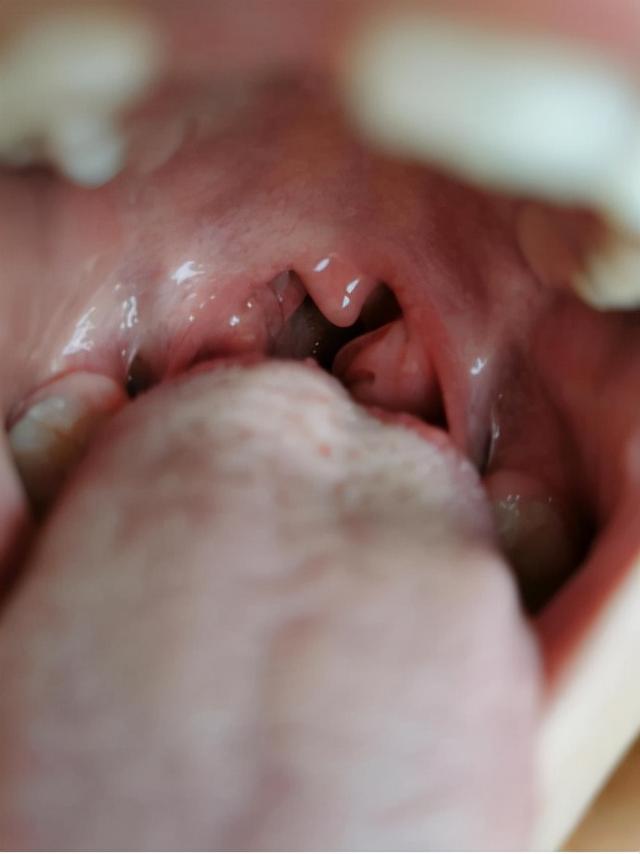

小病人第一次来看病的时候,已经上学了,扁桃体肿到三度的时候,经常发烧感冒,睡觉的时候容易磨牙,睡觉的时候说话,大便变形,有食物残渣,又酸又臭的味道,颜色又黑又粘,需要洗屁股才能擦干净。尿不清,酸重,晨尿酸黄,出现口臭。

图1-就诊前扁桃体肥大的度。

经过几次调理,现在小患者扁桃体已经从III度恢复到正常;体能比之前好,运动后不喊累;做事拖延有好转,上学不迟到;身体也要比以前要强壮一些。夜间磨牙频率降低,之前每天都有。

图16-扁桃体恢复正常